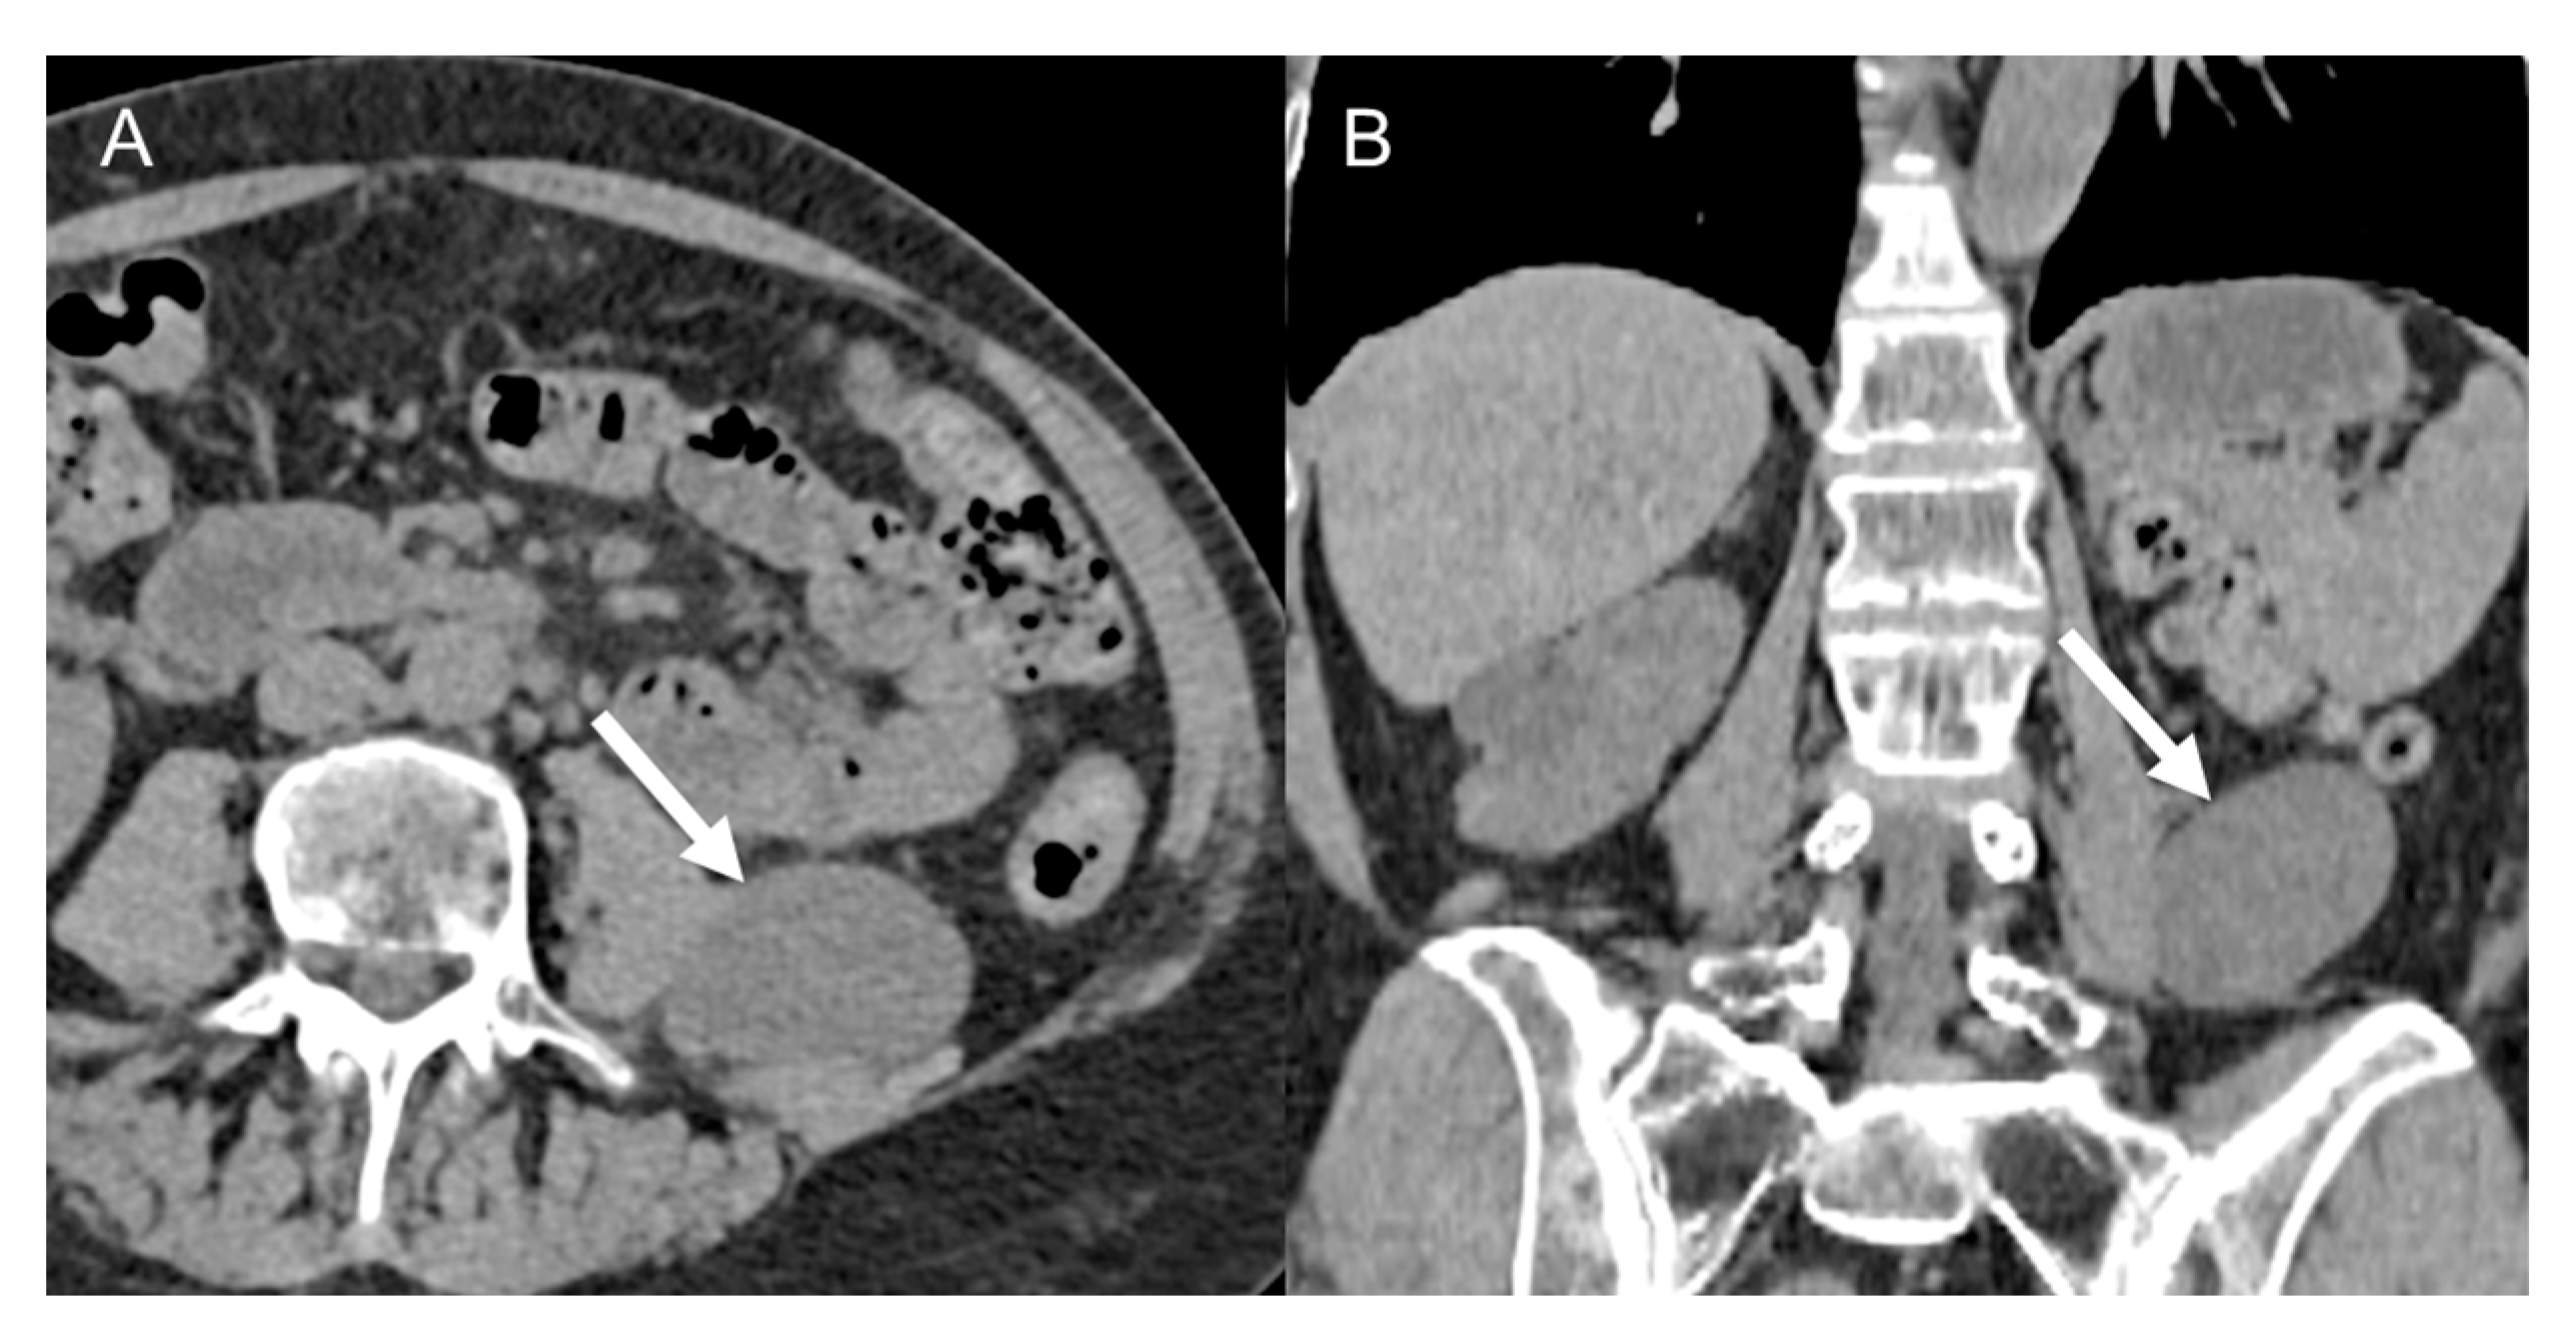

LMS is a smooth muscle tumor [38], more common than LPS in younger age groups [6]. Its most frequent location is the retroperitoneum, near the inferior vena cava [43]. LMS are heterogeneous masses (Figure 4), with irregular peripheral enhancement and enhancing solid portions, mixed with cystic, hemorrhagic, or necrotic areas. LMS show marked T2 hypointensity on MRI and are similar in attenuation to uterine myometrial smooth muscle on CT [39]. Fatty components and calcifications are usually absent [34,38]. The evidence of a large, heterogeneously enhancing, necrotic retroperitoneal mass contiguous with a vessel, with extra- and intraluminal involvement, is highly suggestive of LMS [12,37,43]. It could stem from the inferior vena cava, extending into the intrahepatic portal veins or superior mesenteric vein, or even from small vessels such as renal or gonadic veins. Differentiation from extrinsic compression can be challenging [12,40].

Figure 4.

Retroperitoneal leiomyosarcoma in a 63-year-old woman. Axial (A) and coronal (B) CT images on venous phase show a 10.2 cm heterogeneous mass with central area of low attenuation consistent with necrosis (arrow).